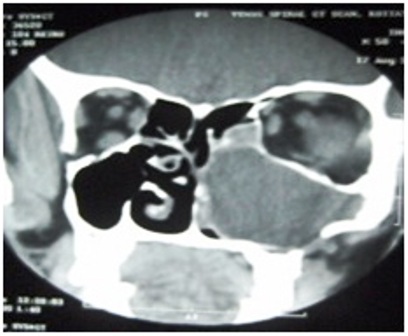

A 50 year old man was referred to our centre on June 2008 with symptoms of nasal blockade and headache of one year duration. Clinical examination showed no abnormality in facial contour, oral cavity or in dental alignment. On further evaluation by CT scan an isodense mass lesion was found involving the whole of the left maxilla with thinning and expansion of the maxillary bone and with extension in the nasal cavity , ethmoids and infratemporal fossa (Fig.1). A punch biopsy was taken endoscopically from the nasal mass. Histopathological examination showed anastomosing strands, basaloid cells around cystic spaces. The cystic spaces showed pale eosinophilic material laden with hemosiderin which supported the diagnosis of plexiform type of ameloblastoma (Fig.2).

Fig.1 CT scan shows soft tissue density lesion with well defined margins in left maxilla with extension into nasal cavity